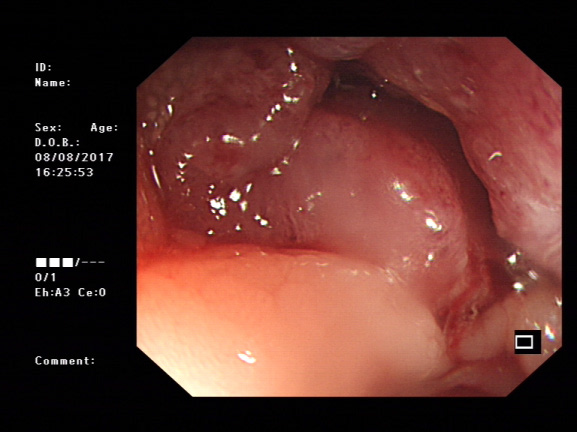

Colonoscopy was performed. The colon became too narrow to pass the scope at 30cms from the anus. Erosive haemorrhagic mucosa was seen and colon cancer was diagnosed. To relieve its obstruction, a stent (80x25mm) was implanted into the narrow lumen. Liquids were then passed through the stent, indicating the obstruction was resolved (Figure 2). One week late, the patient’s general condition became much better and colectomy was performed (Figure 3). The segment with cancer was removed and the patient gained full recovery without complication (Figure 4) and was discharged within one week after colectomy.

Figure 2 Left: sigmoidal colon lesion before inserting stent. Right: after insertion of stent. Liquids were then passed through the stent, indicating the obstruction was resolved.